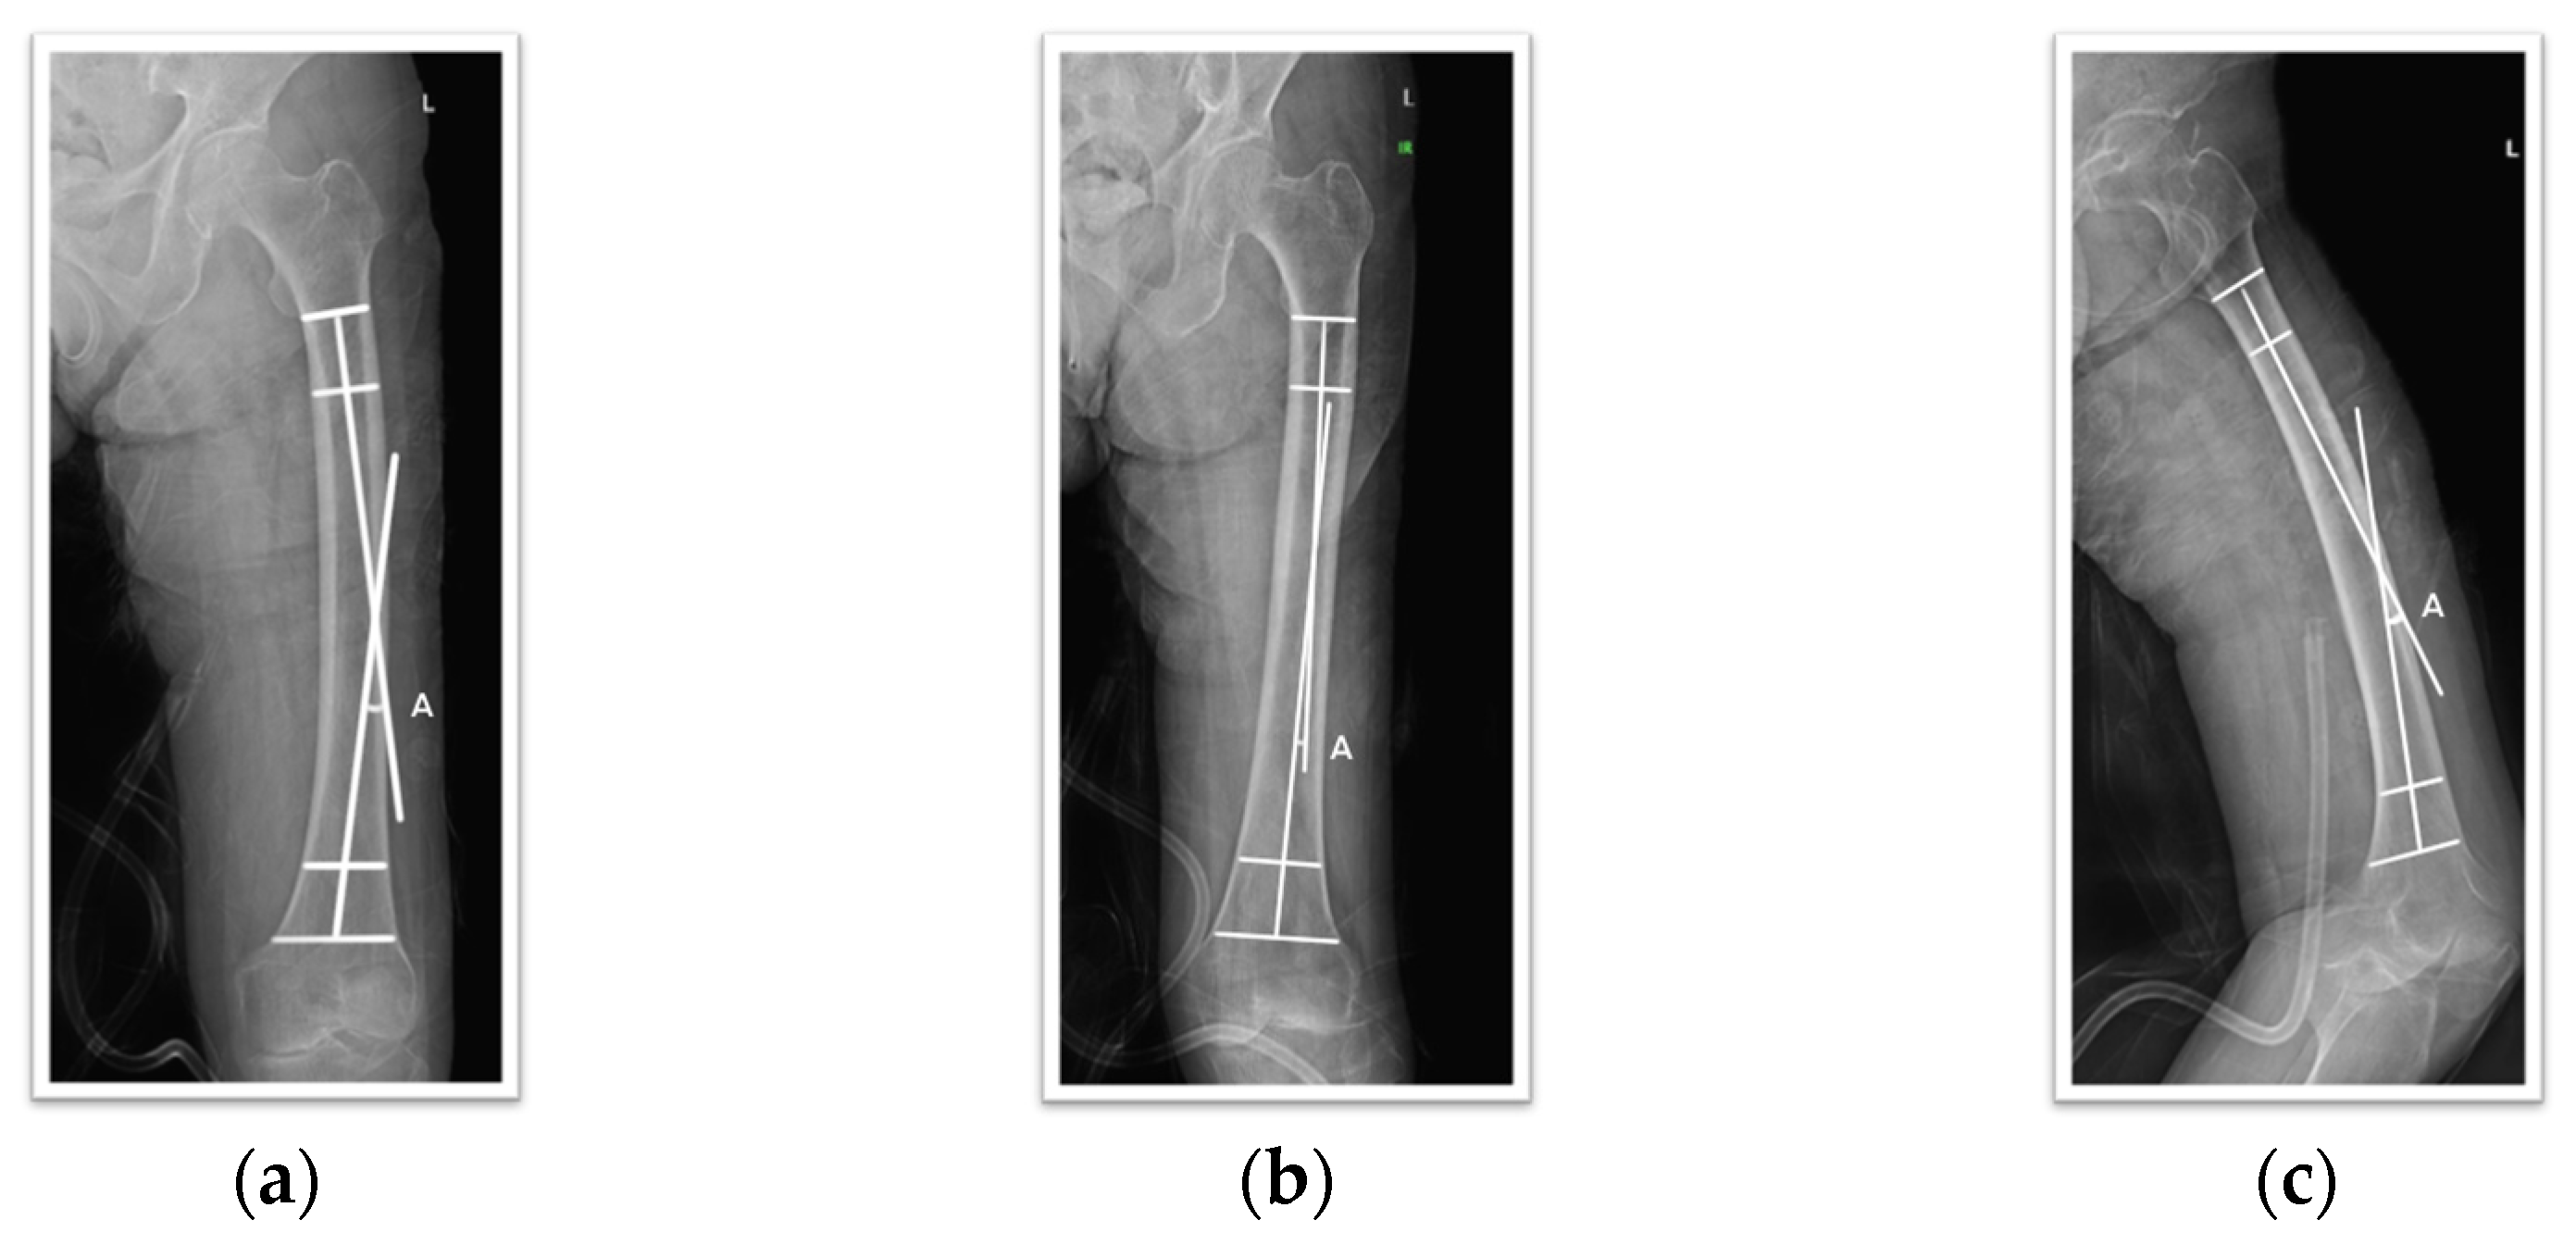

To measure the anterolateral bowing angle, 50 mm long lines bisecting the medullary canal (proximal and distal bisecting lines) were placed at the proximal and distal ends of the defined shaft. The angle formed by the intersection of these two lines was used for measurement. A positive value was defined for bowing in the anterolateral direction, and a negative value was defined for posteromedial bowing. In cases where one leg had previous surgery or pathology, measurements were taken from the healthy contralateral side. All images were captured and measured based on full-length views when possible. This method was applied to AP, lateral, and 15-degree internal rotation views, and the correlation between these results was analyzed (Figure 1).

Figure 1. An example of the measurement method for femoral bowing: (a) AP view; (b) IR view; (c) Lat view.